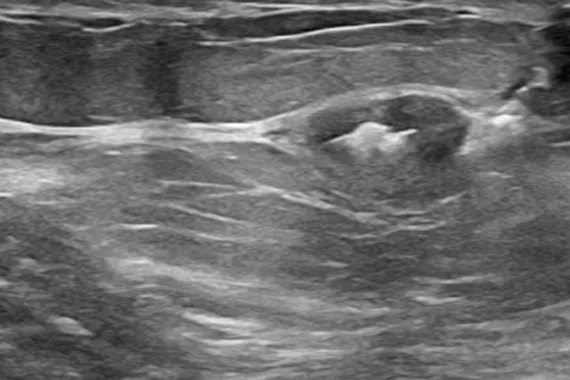

Designed to minimise movement,2 this marker is highly visible in ultrasound upon deployment and still highly visible at 6 weeks post-biopsy, crucial in case of future breast interventions.3 The marker consists of two pieces, a permanent marker and a bioabsorbable suture-like netting.

say ultrasound visibility was good to excellent upon deployment1